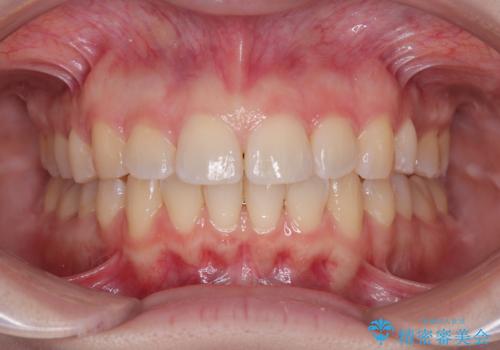

- 「前歯のねじれを改善したい」とのご希望で当院に来院された患者様です。

診察の結果、上下の前歯部に**叢生(そうせい/歯のガタガタ・重なり)**が認められました。

特に上の前歯にはねじれや重なりがあり、審美的にも清掃性にも影響している状態でした。

また、上顎前歯の重なっていた部分にはむし歯が見つかり、治療中に適切な処置を行っています。

矯正治療期間はわずか10か月と、比較的短期間で終了しました。

前歯のデコボコがなくなり、見た目の印象が大きく変わっただけでなく、歯磨きがしやすくなり、むし歯や歯周病のリスクが大きく減少しました。